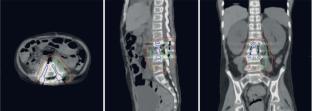

The concept of introducing additional target margins has proven effective in photon radiotherapy and, therefore, is a widely accepted method for ensuring the required dose distribution during planning. However, due to the specific interactions of photon radiation with matter in cases of significant tissue heterogeneity, radiotherapy planning necessitates assessing the robustness of the plan or developing a plan resilient to existing dose delivery uncertainties. This study tested the robustness of radiotherapy plans to geometric uncertainties using two irradiation technologies: CRT (conformal radiation therapy) and IMRT (intensity-modulated radiation therapy). A total of 15 patient plans with metallic prostheses were analyzed. The patient’s position relative to the isocenter of the irradiation beams was geometrically shifted to simulate potential patient setup errors. Data on actual displacements obtained during pretreatment visualization—approximately 25 000 treatment fractions for patients with various tumor localizations—were analyzed. According to the results of the study, the probability of not achieving the required dose distribution for the clinical target volume is no more than \(0.04\pm 0.03\%\) when using the CRT technique and no more than \(7\pm 4\%\) when using IMRT. Thus, the CRT plans demonstrated greater robustness with respect to the target compared to IMRT plans. When IMRT techniques are required for treating patients with prostheses, increased attention must be paid to the patient’s setup and plan robustness verification.